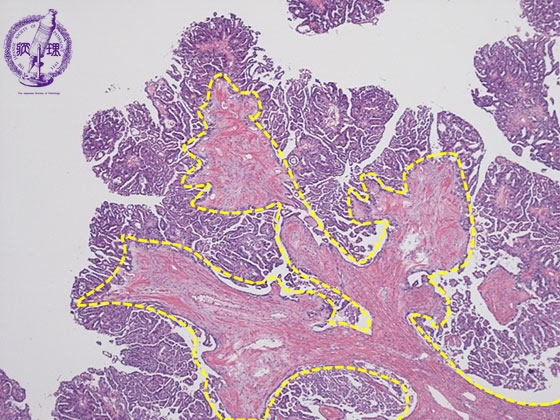

ミクロ像(HE弱拡大):卵巣漿液性嚢胞腺癌。比較的小型で立方状の癌細胞が線維性の間質(黄色点線)を伴いながら乳頭状に増殖している。

• ガイドあり